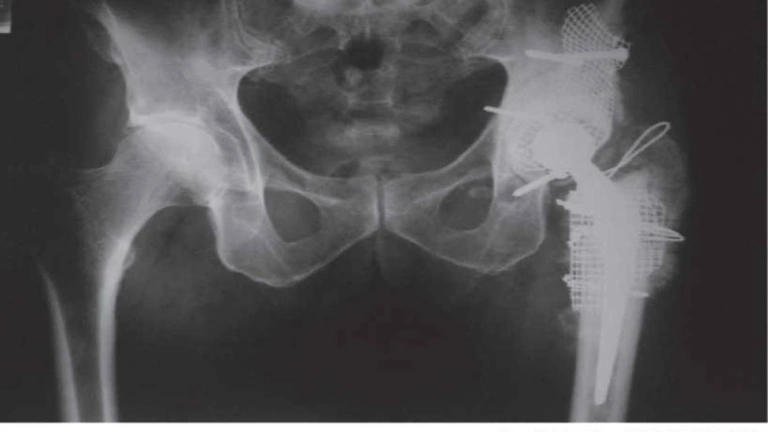

¿Por qué es necesario reconstruir la cadera en un paciente joven?

Esta semana hablamos con el Dr. Fernando Ladero de la reconstrucción de cadera en el paciente joven.